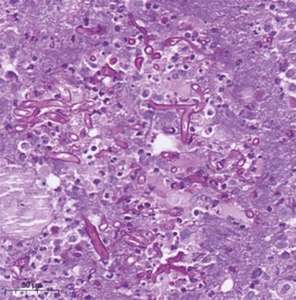

Examination by an ears, nose and throat (ENT) specialist revealed right-sided pansinusitis with black necrotic eschars, suggestive of ROCM. Right orbital decompression and right fronto-spheno-ethmoidectomy were performed. Extensive black eschars were noted intraoperatively (Figure 2). Histopathological examination of the tissue revealed non-septate hyphae branching at 90° angles with associated necrotizing florid inflammation and angioinvasion on haematoxylin and eosin (H&E) (Figure 3) and periodic acid–Schiff (PAS) stained samples, compatible with mucormycosis. Cultures grew of Rhizopus arrhizus. Treatment with high-dose liposomal amphotericin B (10 mg/kg) was initiated. The right orbit was exenterated, the skull base and the pterygopalatine fossa were debrided. The immediate postoperative MRI showed inflammatory progression along the right mandibular and maxillary nerves and into the thrombotic right cavernous sinus, as well as pachymeningeal temporal and frontobasal enhancement (Figure 4). A second-look operation was performed one day later for extended debridement of the right skull base and pterygopalatine fossa. An MRI acquired postoperatively revealed the progression of the infection to the central skull base with perineural spread. Complete removal of all infected tissue would have involved the cavernous sinus, which was considered impossible due to potentially fatal complications. A palliative approach with the best possible medical therapy consisting of high-dose liposomal amphotericin B. Analgesic therapy and stabilization of the metabolic situation was agreed upon. At the patient’s family’s request, a transfer to a hospital in his home country was organized. With liposomal amphotericin B unavailable in Moldova, he was switched to isavuconazole 200 mg/day. 25 days after admission the patient was transferred to Moldova and we lost contact. It was not until approximately a year later that we were able to contact his wife. She told us about the slow and unexpected recovery of her husband, who was now almost symptom-free under posaconazole 300 mg daily, as isovuconazole was not available. He has recently been looking for a job in Germany in order to get insurance that would allow him adequate follow-up that cannot be provided in his home country.

The diagnosis of ROCM is based on microbiological cultures and microscopic evidence from tissue biopsies, as defined by the in 2019 updated European Organization for Research and Treatment of Cancer and the Mycoses Study Group Education and Research Consortium (EORTC).9 Proven MM involves microscopic characteristics like ribbon-like non-septate, right-angle branching hyphae, 200 μm in length, seen in samples treated with special stains (haematoxylin eosin, periodic acid Schiff, Gomori Grocott’s methanamine silver stain), accompanied by evidence of associated tissue damage.10 Cultures are best taken from tissue samples rather than swabs.4,11 There is no application for serologic testing. Quantitative polymerase chain reaction (PCR) is available, but not yet part of clinical daily use. There are no reliable markers in MM.